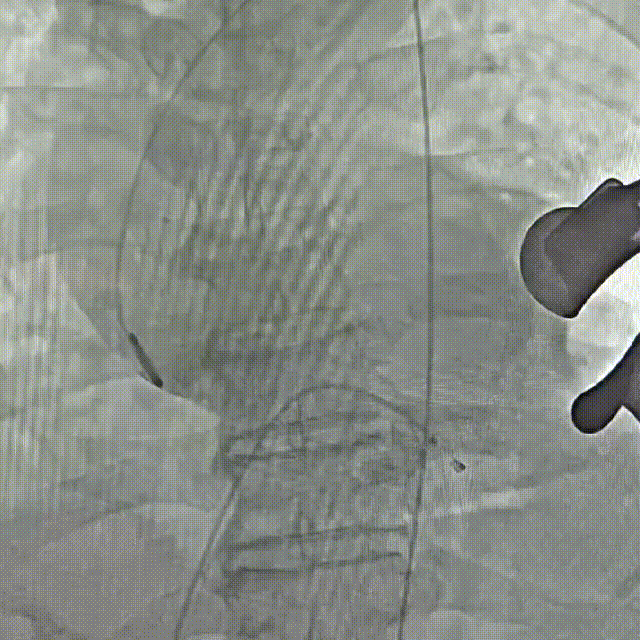

瓣膜0位定位释放

瓣膜稳定释放至全展开,无明显下滑,位置稳定

造影评估,瓣膜位于瓣下2mm形态稳定

左冠切线评估,小弯侧深度6mm

无张力脱钩,瓣膜无位移

最终造影,无瓣周漏